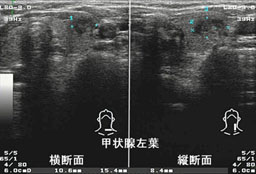

超音波所見:甲状腺左葉に10.6×15.4×8.4mm

辺縁不整 境界不明瞭 モザイク様腫瘤認める